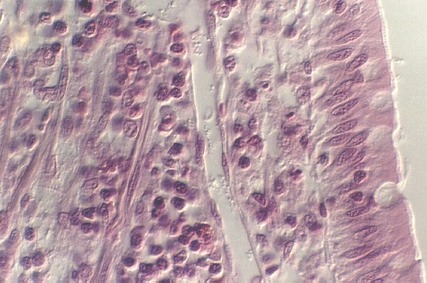

The epithelium of the duodenum consists of the COLUMNAR ABSORPTIVE CELLS interspersed with GOBLET CELLS. In the following photograph, these cells are evident along with their BRUSH BORDER. Underneath the epithelium, the lamina propria can be seen. Identify these cells and regions on the appropriate photographs:

The following photo shows a better view of the lamina propria which is the core of the villi. Strands of smooth muscle, vessels, and numerous cells typical of connective tissue are found in this region.